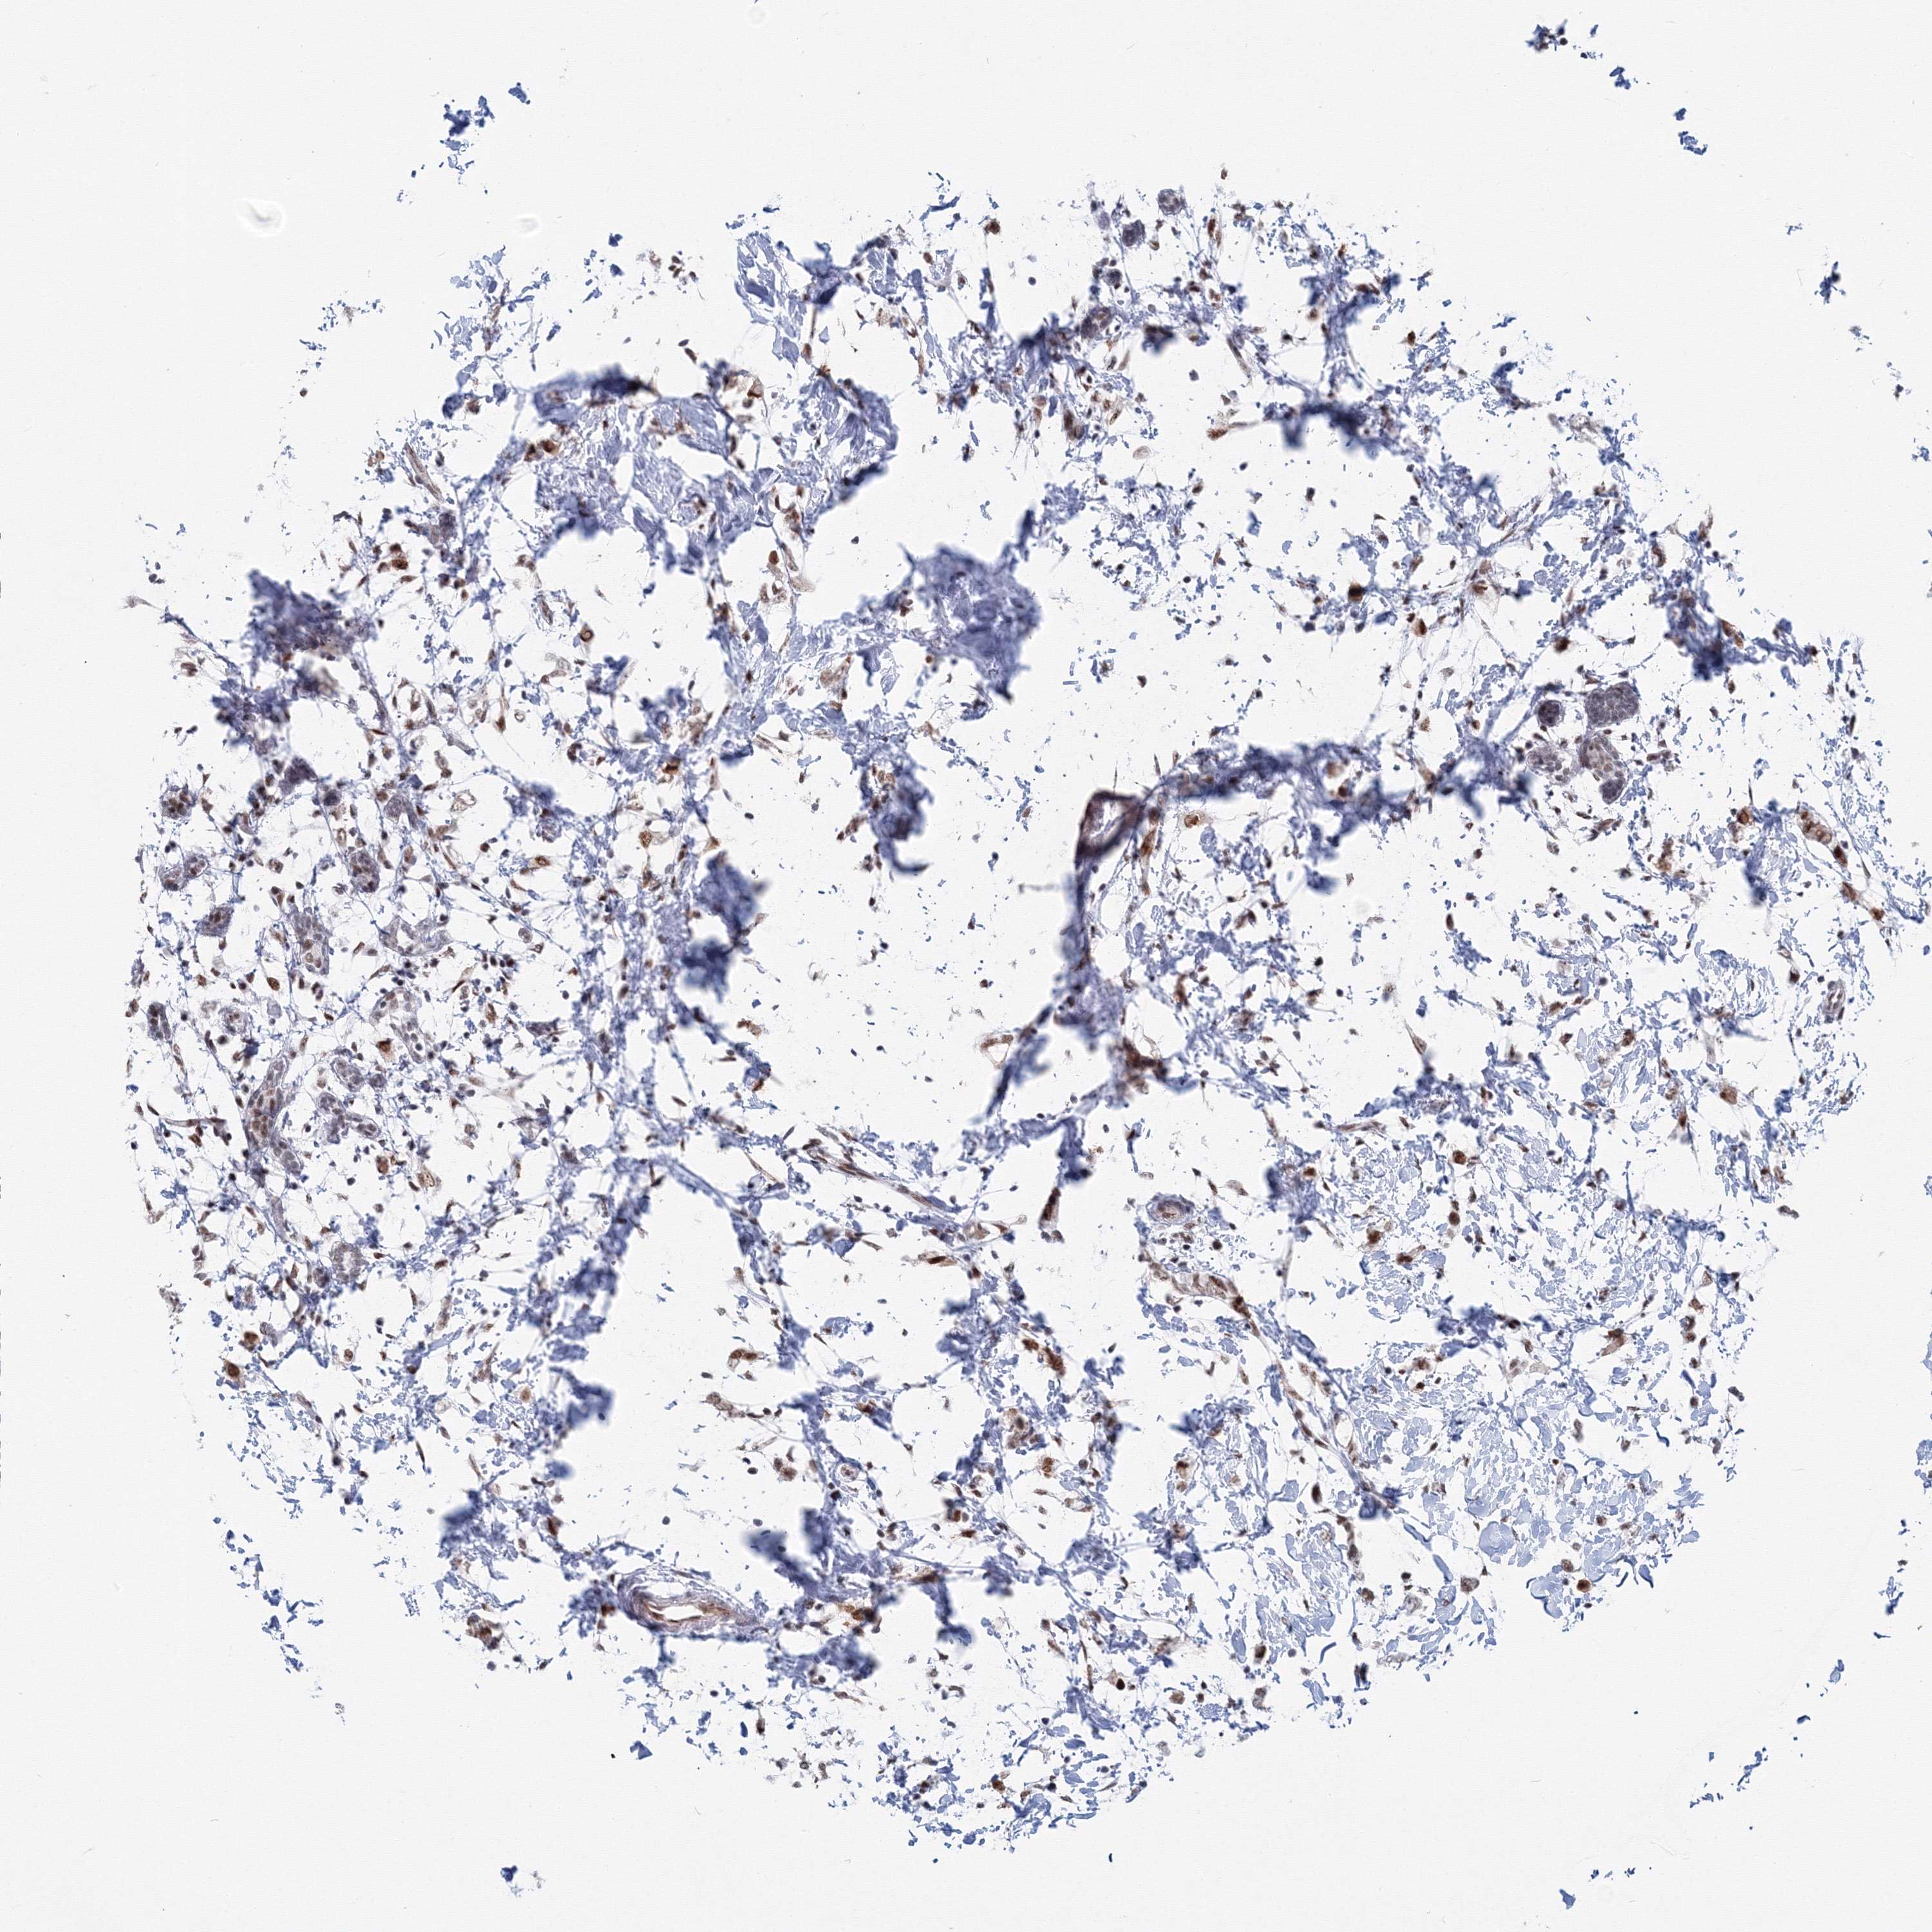

CANCER BREAST CANCER Show tissue menu

BRCA TCGA BRCA VALIDATION PROTEIN EXPRESSION

ANTIBODIES

AND

VALIDATION